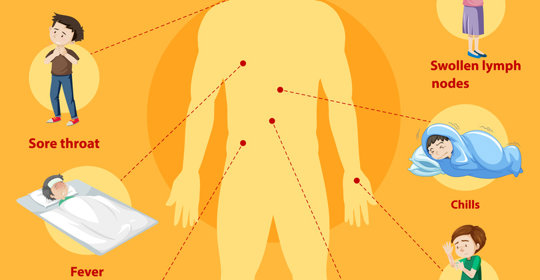

腦實質浸潤:症狀與治療

腦實質浸潤:症狀與處理

腦實質的浸潤:病因與治療方法